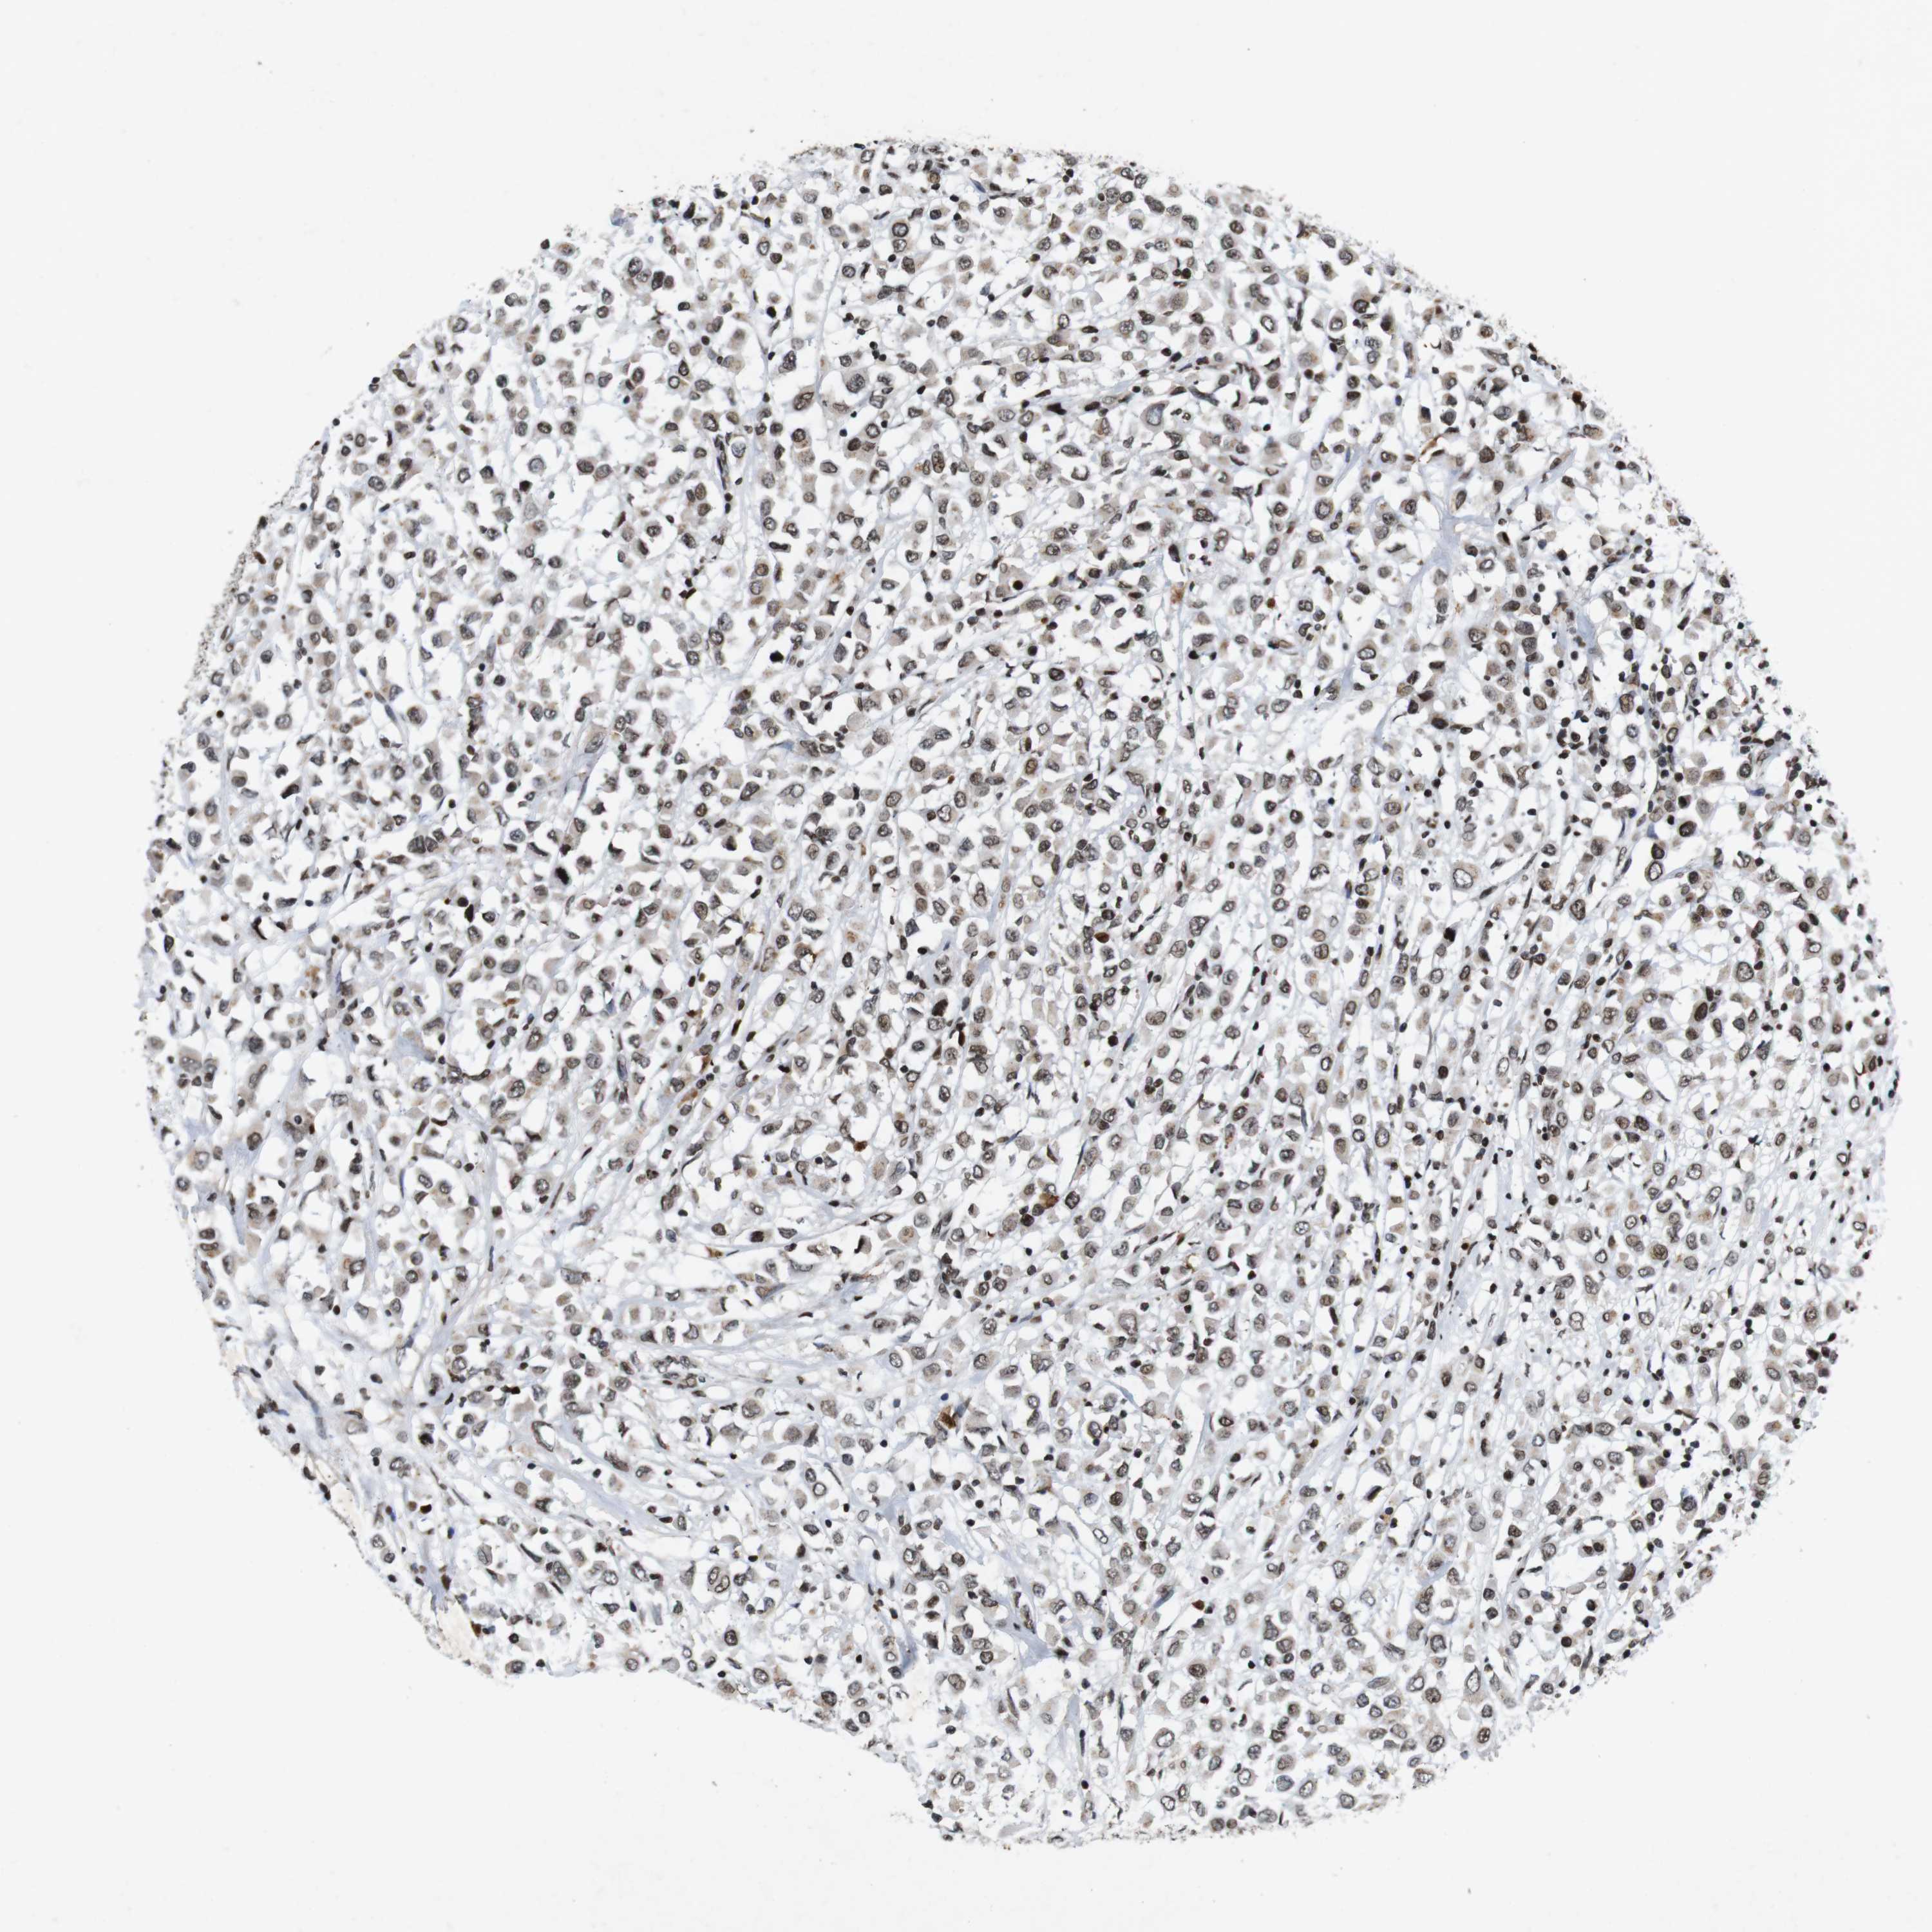

CANCER BREAST CANCER Show tissue menu

BRCA TCGA BRCA VALIDATION PROTEIN EXPRESSION